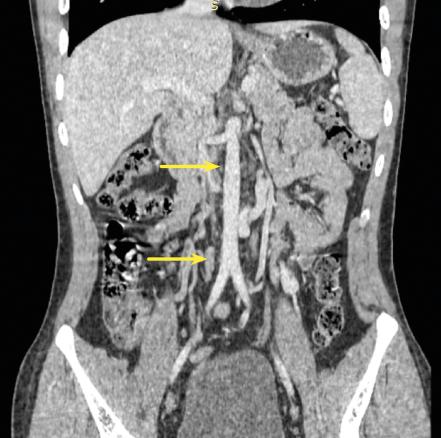

L’échographie Doppler veineuse des membres inférieurs montre une thrombose primitive de l’axe veineux iliaque, interne et externe gauche, sur tout le trajet. Devant l’étendue de la thrombose, un angioscanner abdomino-pelvien est réalisé (figure), révélant une agénésie de la veine cave inférieure infra-rénale avec déploiement de multiples collatérales veineuses pelviennes et périrénales. Un traitement anticoagulant a permis une évolution favorable.